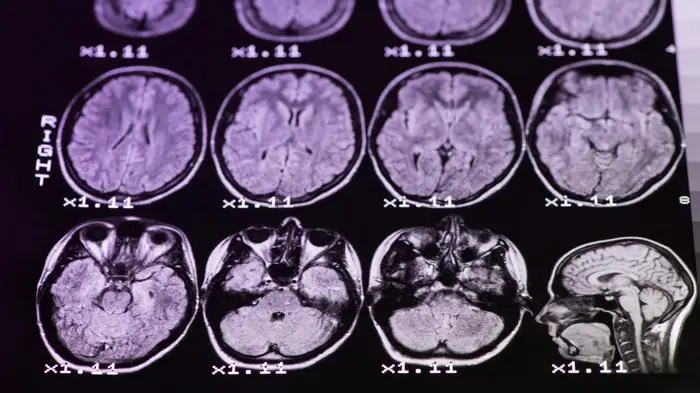

Multiple Sklerose: Körpereigene Immunzellen greifen das zentrale Nervensystem an